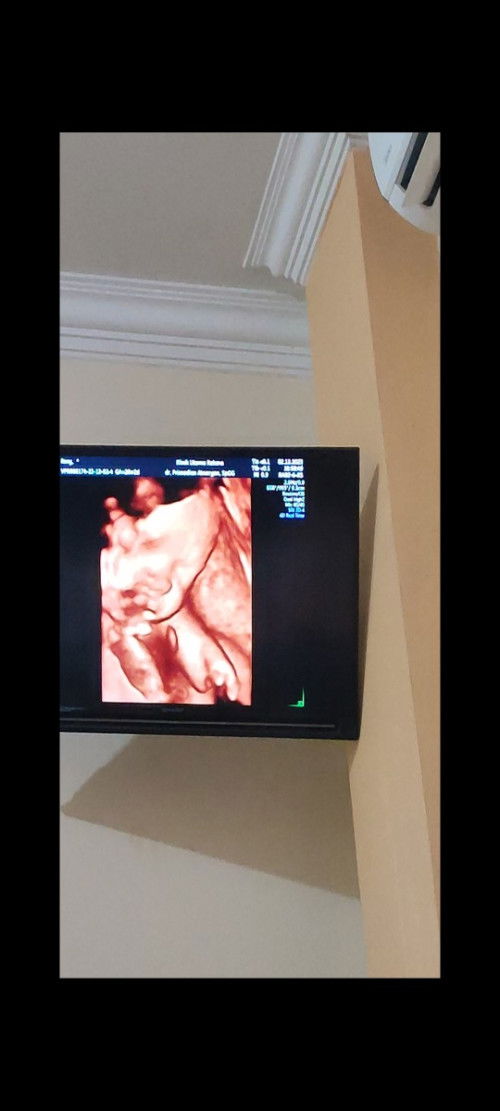

Hasil usg tangan janin

Hasil usg tangan janin kaya di foto,bunda2 ada yg hampir mirip ga?itu normal kan bun? Soalnya td lupa tanya kedokter kontrol sendirian,suami mnta dividio jdi baru nggeh pas dirumah ini kepikiran bgt sm tangan si dede🥺 #firstmom #seriusnanya #ingintahu